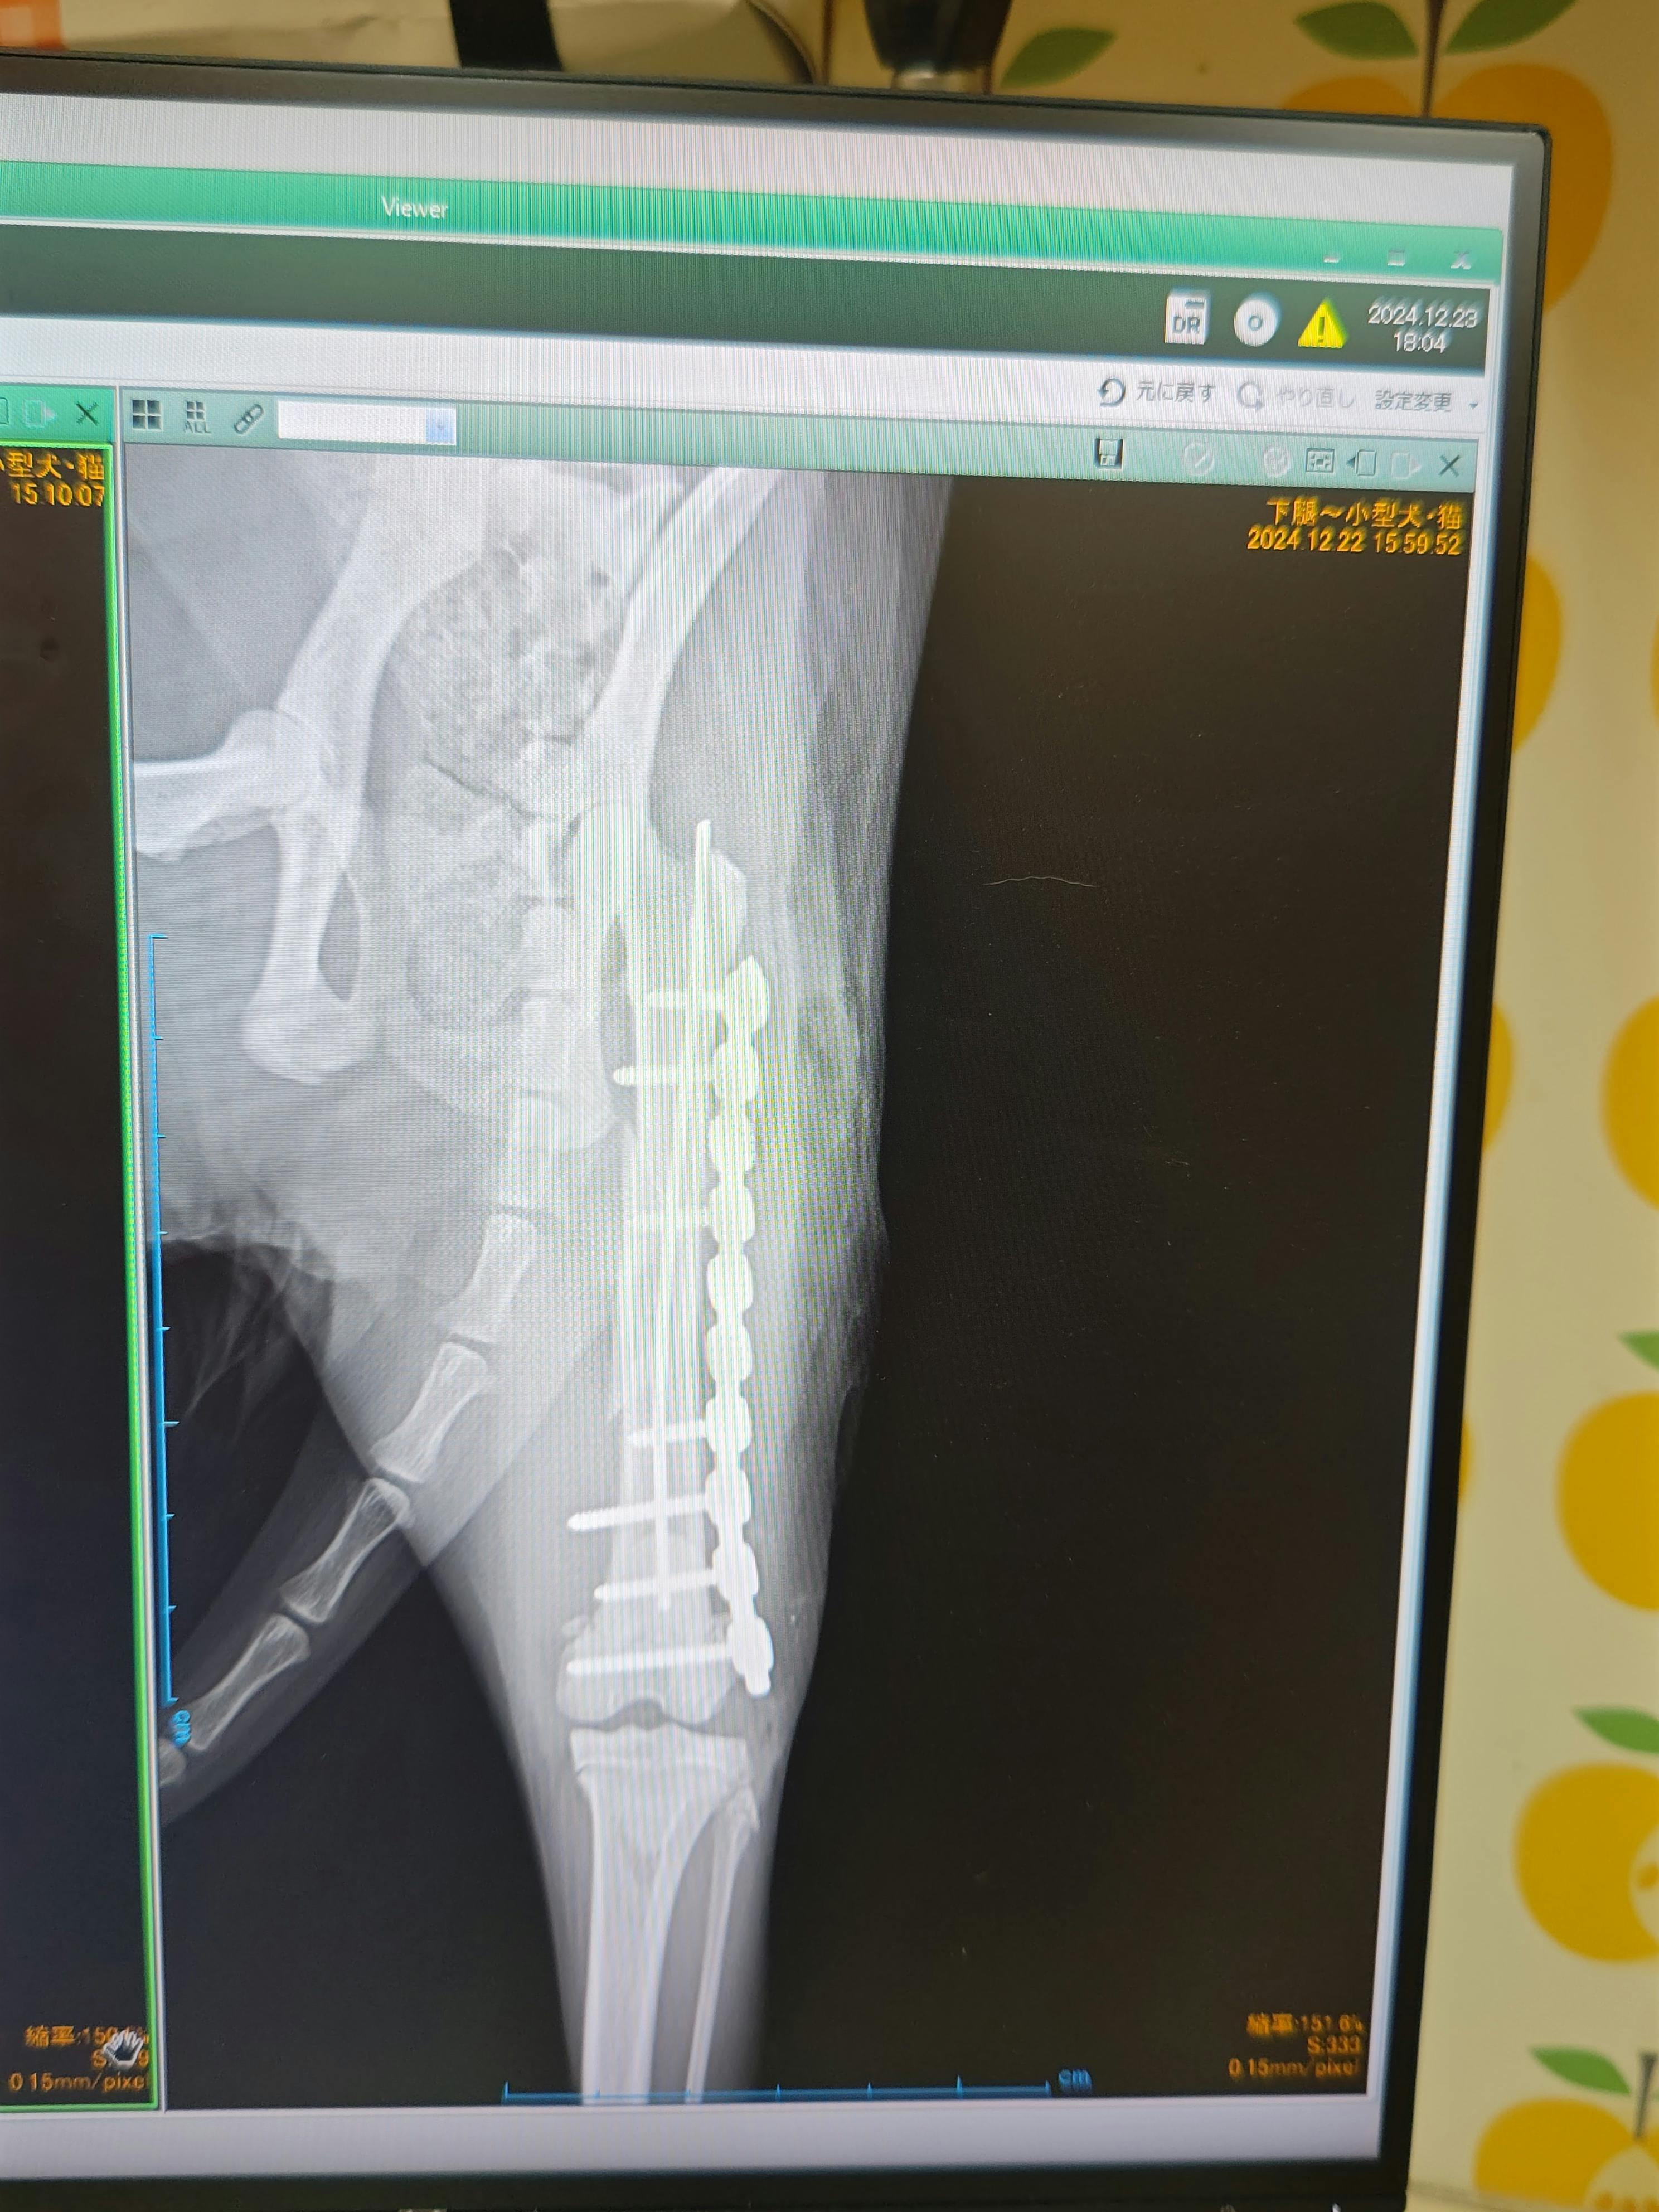

左大腿部螺旋骨折でオペした真珠ちゃんが元気に走れました!

元々、運動能力の高さが災いしての骨折でした

何とか元のようにしてやりたい。その願いが叶いました。

まだまだ、オペから1か月後のレントゲンまでは油断無く、少しずつ日常生活のリハビリをします。